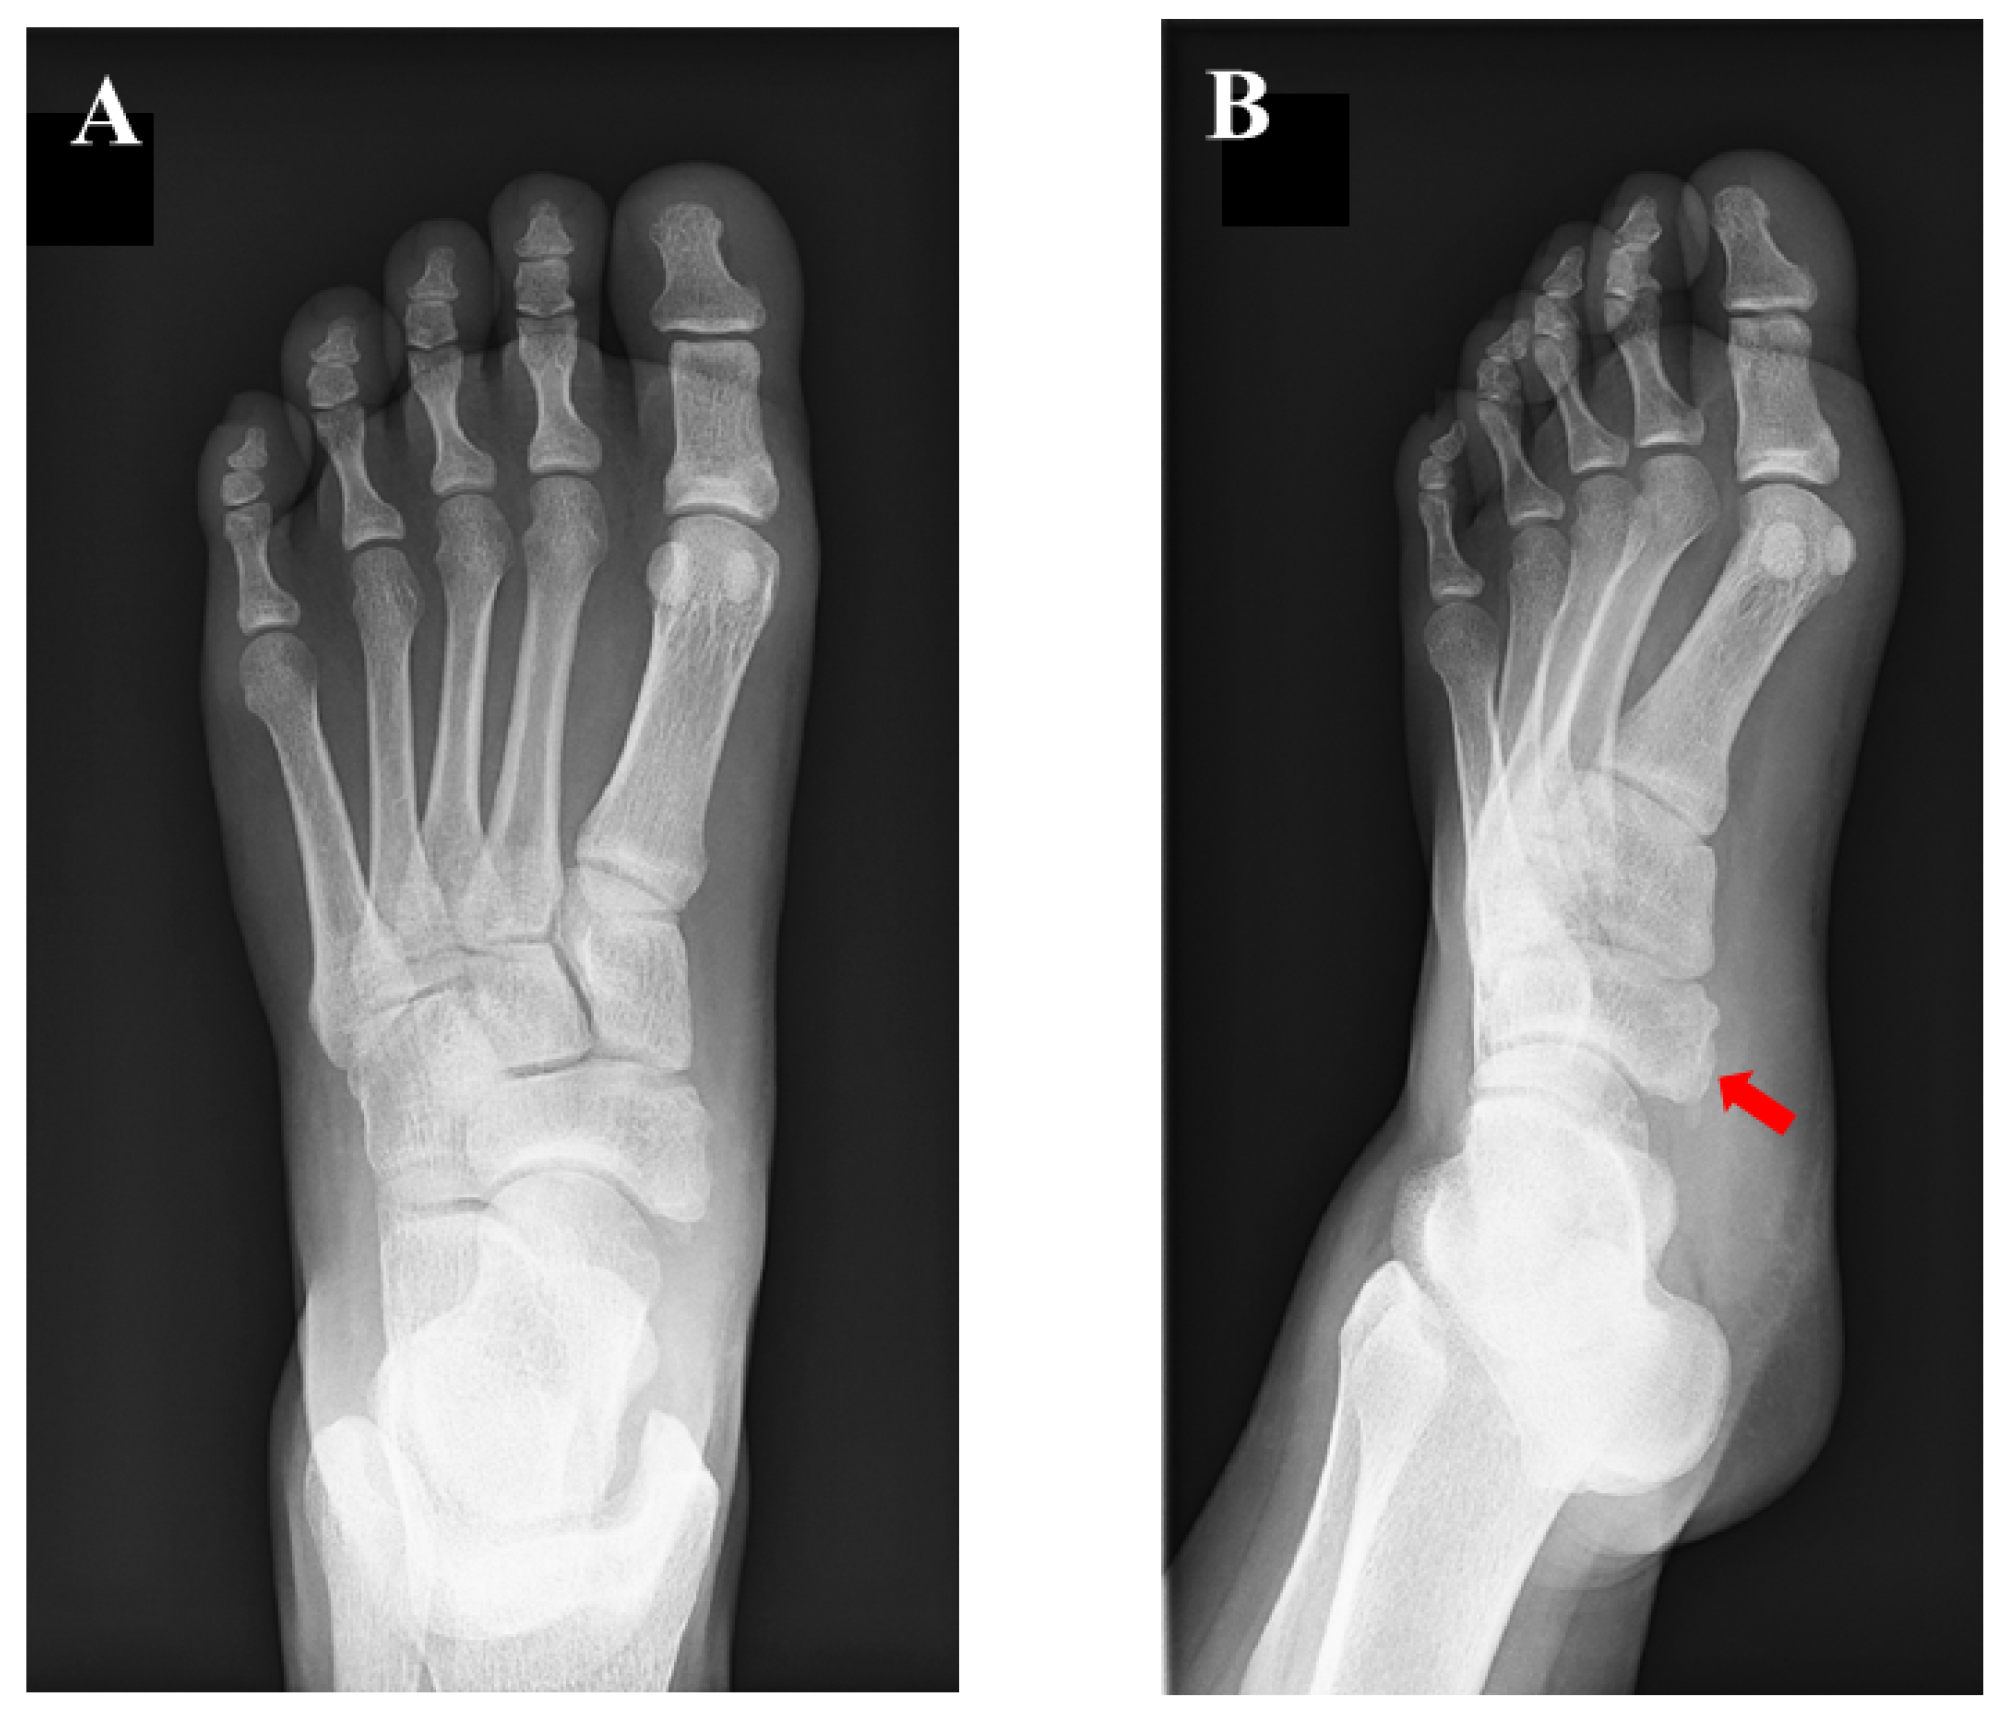

A 15-year-old girl was referred to our department for the assessment of left foot pain. She was diagnosed with AN, which was radiographically classified as Veitch type Ⅰ at a private orthopedic clinic (Figure 1).

Figure 1.

Preoperative plain radiographic findings: (A) anteroposterior view and (B) oblique view. The red arrow indicates the accessory navicular (AN). The AN was classified as type 1, according to the Veitch classification.